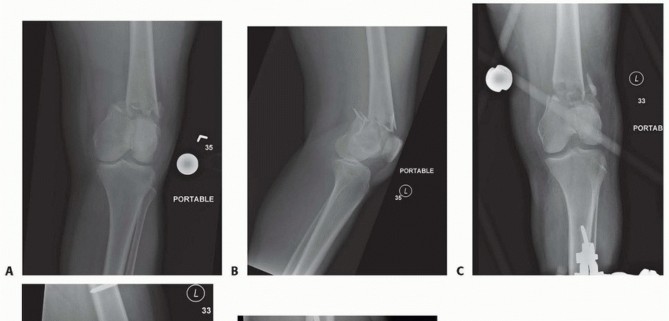

### FIG 5 • A-C. Patient with a spiral distal-third femur fracture that appears to be extra-articular. A. In the AP radiograph, the knee is not fully visualized. B. A dedicated knee AP radiograph shows the spiral distal-third femur fracture. Note the intra-articular injury and the gap at the fracture (arrows). C. Lateral view of the knee. Again note the coronal fracture of the medial femoral condyle (type B3). D-F. Plain radiographs of a patient with a grade II open distal femur fracture. G,H. Patient with a dosed femur fracture that was initially thought to be extra-articular. 470

### FIG 6 • A. Axial CT image of patient in FIG 5A-C confirming the type B3 fracture of the medial femoral condyle. B. Axial CT image of the patient in FIG 5D-F. C-E. CT images of the patient in FIG 5G,H show the nondisplaced intercondylar split as well as the low lateral fracture line and extensive posterior metaphyseal comminution (type C2).

TECH FIG 11 • Patient with closed distal femur fracture (also shown in FIG 5G,H and 6C-E). A. Limited lateral incision, with the tibial tubercle marked. B. Skin incision showing the iliotibial band. C. Incision of the iliotibial band. D. Exposure of the lateral aspect of the femur. 487 ### Stabilizing the Articular Surface For nondisplaced type C1 or C2 fractures, the first priority is to stabilize the articular surface. Visualization of the joint may be accomplished with placement of a blunt Hohmann retractor (or similar Z retractor) ( TECH FIG 12A).

### TECH FIG 12 • A. Visualization of the joint for articular reduction. B. C-arm image of reduction forceps holding the intercondylar split reduced. C,D. Clinical photographs with forceps followed by guidewires for screw placement. E,F. Lateral views showing pins and wires outside the zone for either plate application or intramedullary nail. The anterior and posterior placement of the pins is seen. (continued) A reduction forceps is placed anteriorly to hold the reduction ( TECH FIG 12B). Temporary Kirschner wires or guidewires from a cannulated system can be placed for additional stability ( TECH FIG 12C,D). All clamps, Kirschner wires, or guidewires should be placed outside the zone of plate application ( TECH FIG 12E,F). 488

--- - TECH FIG 12 • (continued) G. Definitive fixation of the condyles with 4.5-mm partially threaded cannulated screws. Definitive fixation of the condyles should be performed (see technique description earlier) ( TECH FIG 12G). ### Reduction of the Distal Segment and Plate Placement Reduction of the distal segment to the shaft can be performed using temporary Steinmann pins ( TECH FIG 13). The plate can now be applied in a submuscular fashion (see Placement of the Plate section earlier). ### Wound Closure Final radiographs are taken in the operating room ( TECH FIG 14). Standard wound closure is undertaken, as described in the previous section. ### Retrograde Nailing(FIG 10A-F) Refer to Chapter 43 on retrograde nailing of the femur.